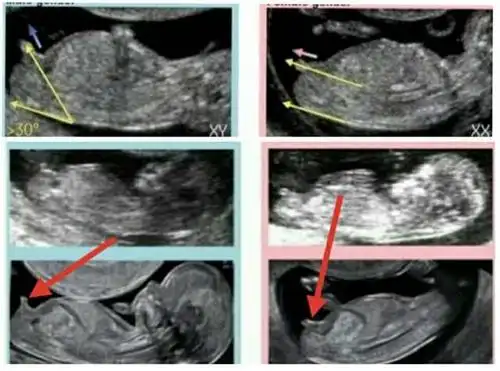

12周nt男宝特点

12周胎儿男女生殖图区别图

nt12周看见小丁丁了很神奇很准的nt看男女方法

孕3月男女胎儿个性藏得深,摸清b超这几个数据,胎儿就没啥秘密了